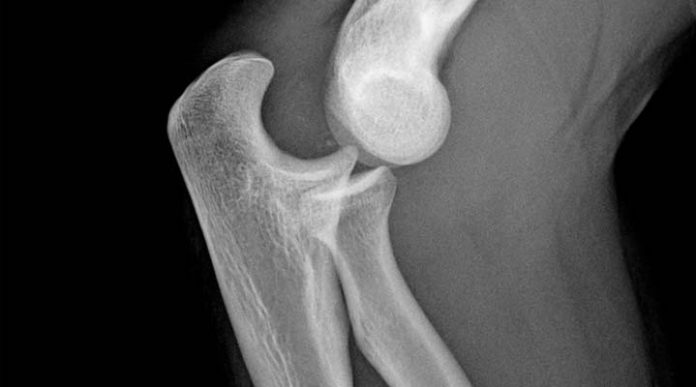

El descubrimiento se ha centrado en las microfracturas óseas, debido a que «en las roturas a mayor escala, el proceso de regeneración celular es distinto», comentó Catalán.

Estas microfracturas se pueden producir con el uso normal del hueso, aunque en deportistas de alto rendimiento son más frecuentes.

Una vez se produce esta microscópica rotura, la presión que se aplica sobre el punto inicial de la fractura es la que genera flexoelectricidad, es decir, que produce una descarga que mata las células de su alrededor.